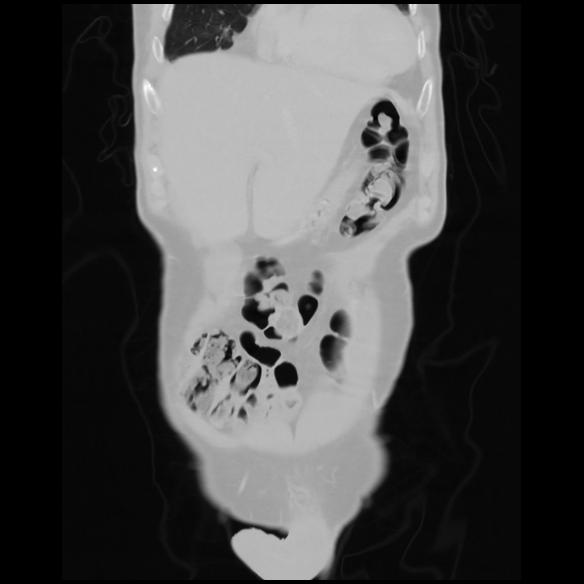

6 CUERPO,CE,Coronal,3.000,CUERPO,Coronal,